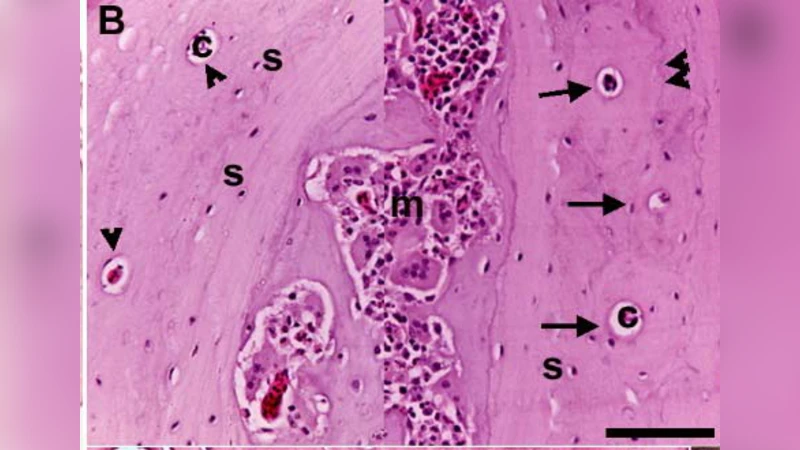

첫 번째 주요 결과는 파충류 골 조직의 혈관 분포 차이다. 지구라시의 골 조직은 거의 무혈관성(avascular)이며, 골세포(lacunae)와 골소관(vascular canal)이 거의 관찰되지 않는다. 반면 나일 모니터는 고도로 혈관화된 구조를 보여, 원시 골소관(primary vascular canals)이 풍부하고, 이들 주변에 불규칙하게 배열된 골세포가 존재한다. 이는 파충류 내에서도 서식 환경·대사 요구에 따라 골 혈관화 정도가 크게 달라질 수 있음을 시사한다.

두 번째로, 조류의 경우는 종마다 차이를 보인다. 참새의 골 조직은 한쪽 면은 혈관이 풍부하고, 반대쪽 면은 거의 무혈관성을 나타내어, 골의 비대칭적 혈관 분포가 가능함을 보여준다. 오리와 거위는 대부분의 골 조직이 ‘dense Haversian tissue’라 불리는 고밀도 하버시안 조직으로 구성되어 있으나, 이 조직 역시 전형적인 포유류 하버시안 시스템과는 차이가 있다. 구체적으로는 골소관이 비교적 넓고, 골세포가 불규칙하게 배열된 원시 골소관(primary osteons)이 일부 영역에 국한되어 존재한다.